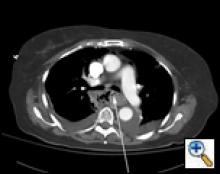

A 79 year-old female presented to an outside institution with a one day history of epigastric and retrosternal pain in the summer of 2005. She had no complaints of fever, emesis, hematemesis, retching, weight loss, odynophagia, or dysphagia. Her past medical history included hypothyroidism and stable coronary artery disease. She was thought to have acute cholecystitis, and seven days later developed respiratory distress and a chest X-Ray revealed mediastinal air and a right-sided pleural effusion. Computed tomography (CT) scan of the chest showed a large fluid collection around the distal esophagus tracking into the right chest, a possible intraluminal mass and air within the wall of the esophagus (Figure 1). A chest tube was placed in the right chest which drained culture-negative serosanguinous fluid. A gastrograffin swallow revealed an esophageal perforation with free-flow of contrast into the right chest (Figure 2). The patient was transferred to our institution with the diagnosis of esophageal perforation.